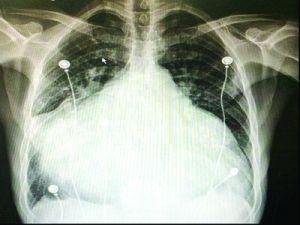

1999年,國外專家首先將其套用於瓣膜病導致過大左心房的治療。而2010年,北京協和醫院才在國內首開先河,開展了首例原位自體心臟移植。

2012年8月23日,南京鼓樓醫院成功實施華東首例自體心臟移植術。